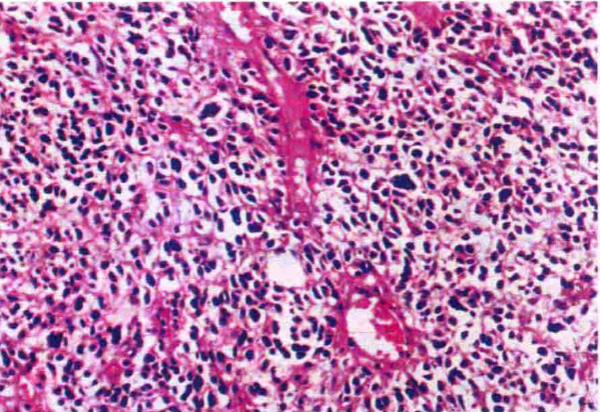

是中枢神经系统中最常见的胚胎性肿瘤,占原发性颅内肿瘤的2%~4%,占神经上皮组织肿瘤的7%~8%。高峰发病年龄为7岁,其次为10~16岁,50岁以上罕见。髓母细胞瘤均发生于小脑,75%的儿童髓母细胞瘤发生于小脑蚓部,并突入第四脑室;部分病例可发生于小脑半球。此瘤为高度恶性肿瘤,WHO Ⅳ级。

肉眼观,肿瘤组织使小脑蚓部或半球肿大,切面呈鱼肉状,色灰红或暗红,边界不清,可见出血、坏死。镜下,肿瘤由圆形、椭圆形或胡萝卜形细胞构成,胞核着色深,胞质少而边界不清楚,有多少不等的核分裂象。